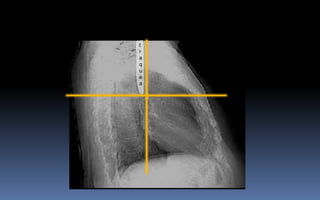

INDICE CARDIOTORACICO NORMAL

valor normal es igual o inferior a 0.5 varia según el biotipo y edad del

paciente. (línea roja / suma de líneas azules )